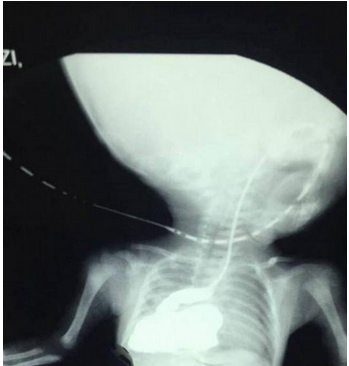

西安市儿童医院新生儿外科主治医师卢朝祥:“这个孩子诊断是食管裂孔疝,从片子可以看到他的胃在胸腔里,正常人胃在肚子里。”

因为盼盼的食管裂孔非常大,导致了他的胃跑到了胸腔里,而食管裂孔疝是小儿外科常见的一种发育畸形。